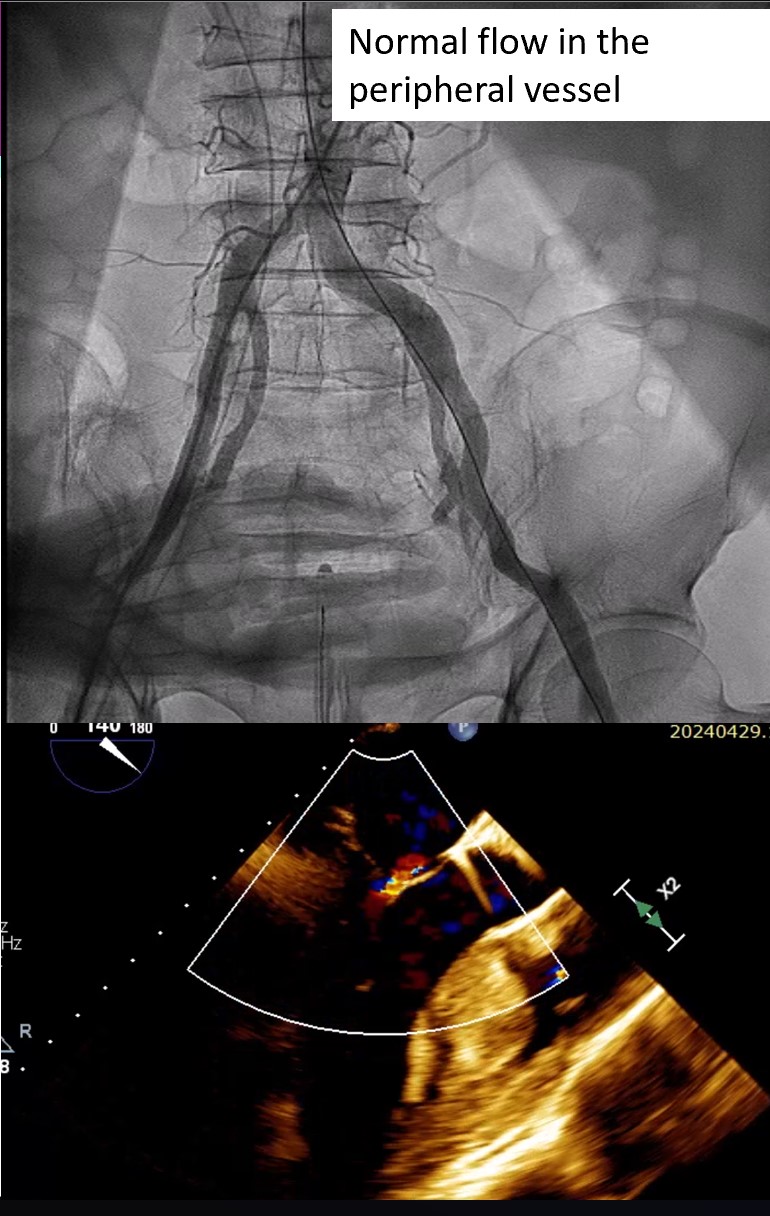

Relevant Catheterization Findings

First, through the right femoral vein, the Neoblazar® delivery system (Dawneo Neoblazar, Hangzhou, China) was advanced till the tricuspid valve, and two clips (TMrCLAMP-S) were deployed to grasp the anterior and septal leaflets with a desired outcome reducing to a mild residual TR. Postoperative VC width was 0.2cm with EROA of 0.17cm2 and regurgitation volume of 15mL. The delivery system removed and 18 fr sheath exchanged. A 5 fr temporary pacemaker wire positioned through sheath into the right ventricle. Subsequently, the right and left femoral arteries were each accessed with 6-fr sheath and 22 fr sheath respectively. Through the left femoral artery, the TAVI delivery system with a 30mm VitaFlow Liberty™ self-expanding valve system (MicroPort®, Shanghai, China) was advanced across the aortic valve and deployed under transoesophageal and fluoroscopic guidance with rapid ventricular pacing at 140 beats/minute and pacing slowly tapered. The mean valvular gradient after TAVI decreased to 6 mmHg. Then, percutaneous access closure of arterial access was achieved using a pre-closure technique with the suture-mediated ProGlide device (Abbott Laboratories Inc., Chicago, Illinois, United States). The total procedure time was 60min. There were no intraoperative complications. The temporary pacemaker was removed two days later. Predischarge transthoracic echocardiogram showed a normal functioning aortic THV with a mean gradient of 6mmHg and mild residual tricuspid regurgitation.